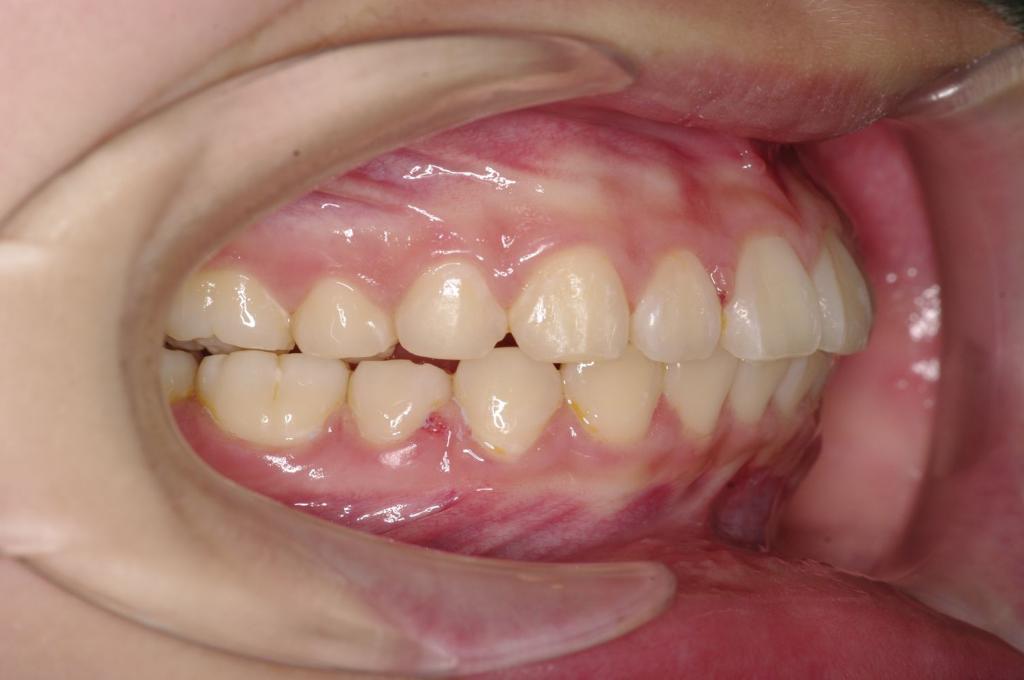

前歯、出っ歯・開咬の矯正治療

(治療期間、治療前後写真、治療方法、費用)WORKS